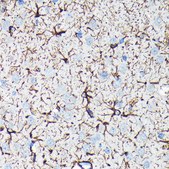

immunofluorescence: 1:50 - 1:200, immunohistochemistry: 1:50 - 1:200, western blot: 1:500 - 1:2000

WB, IHC, IF/ICC